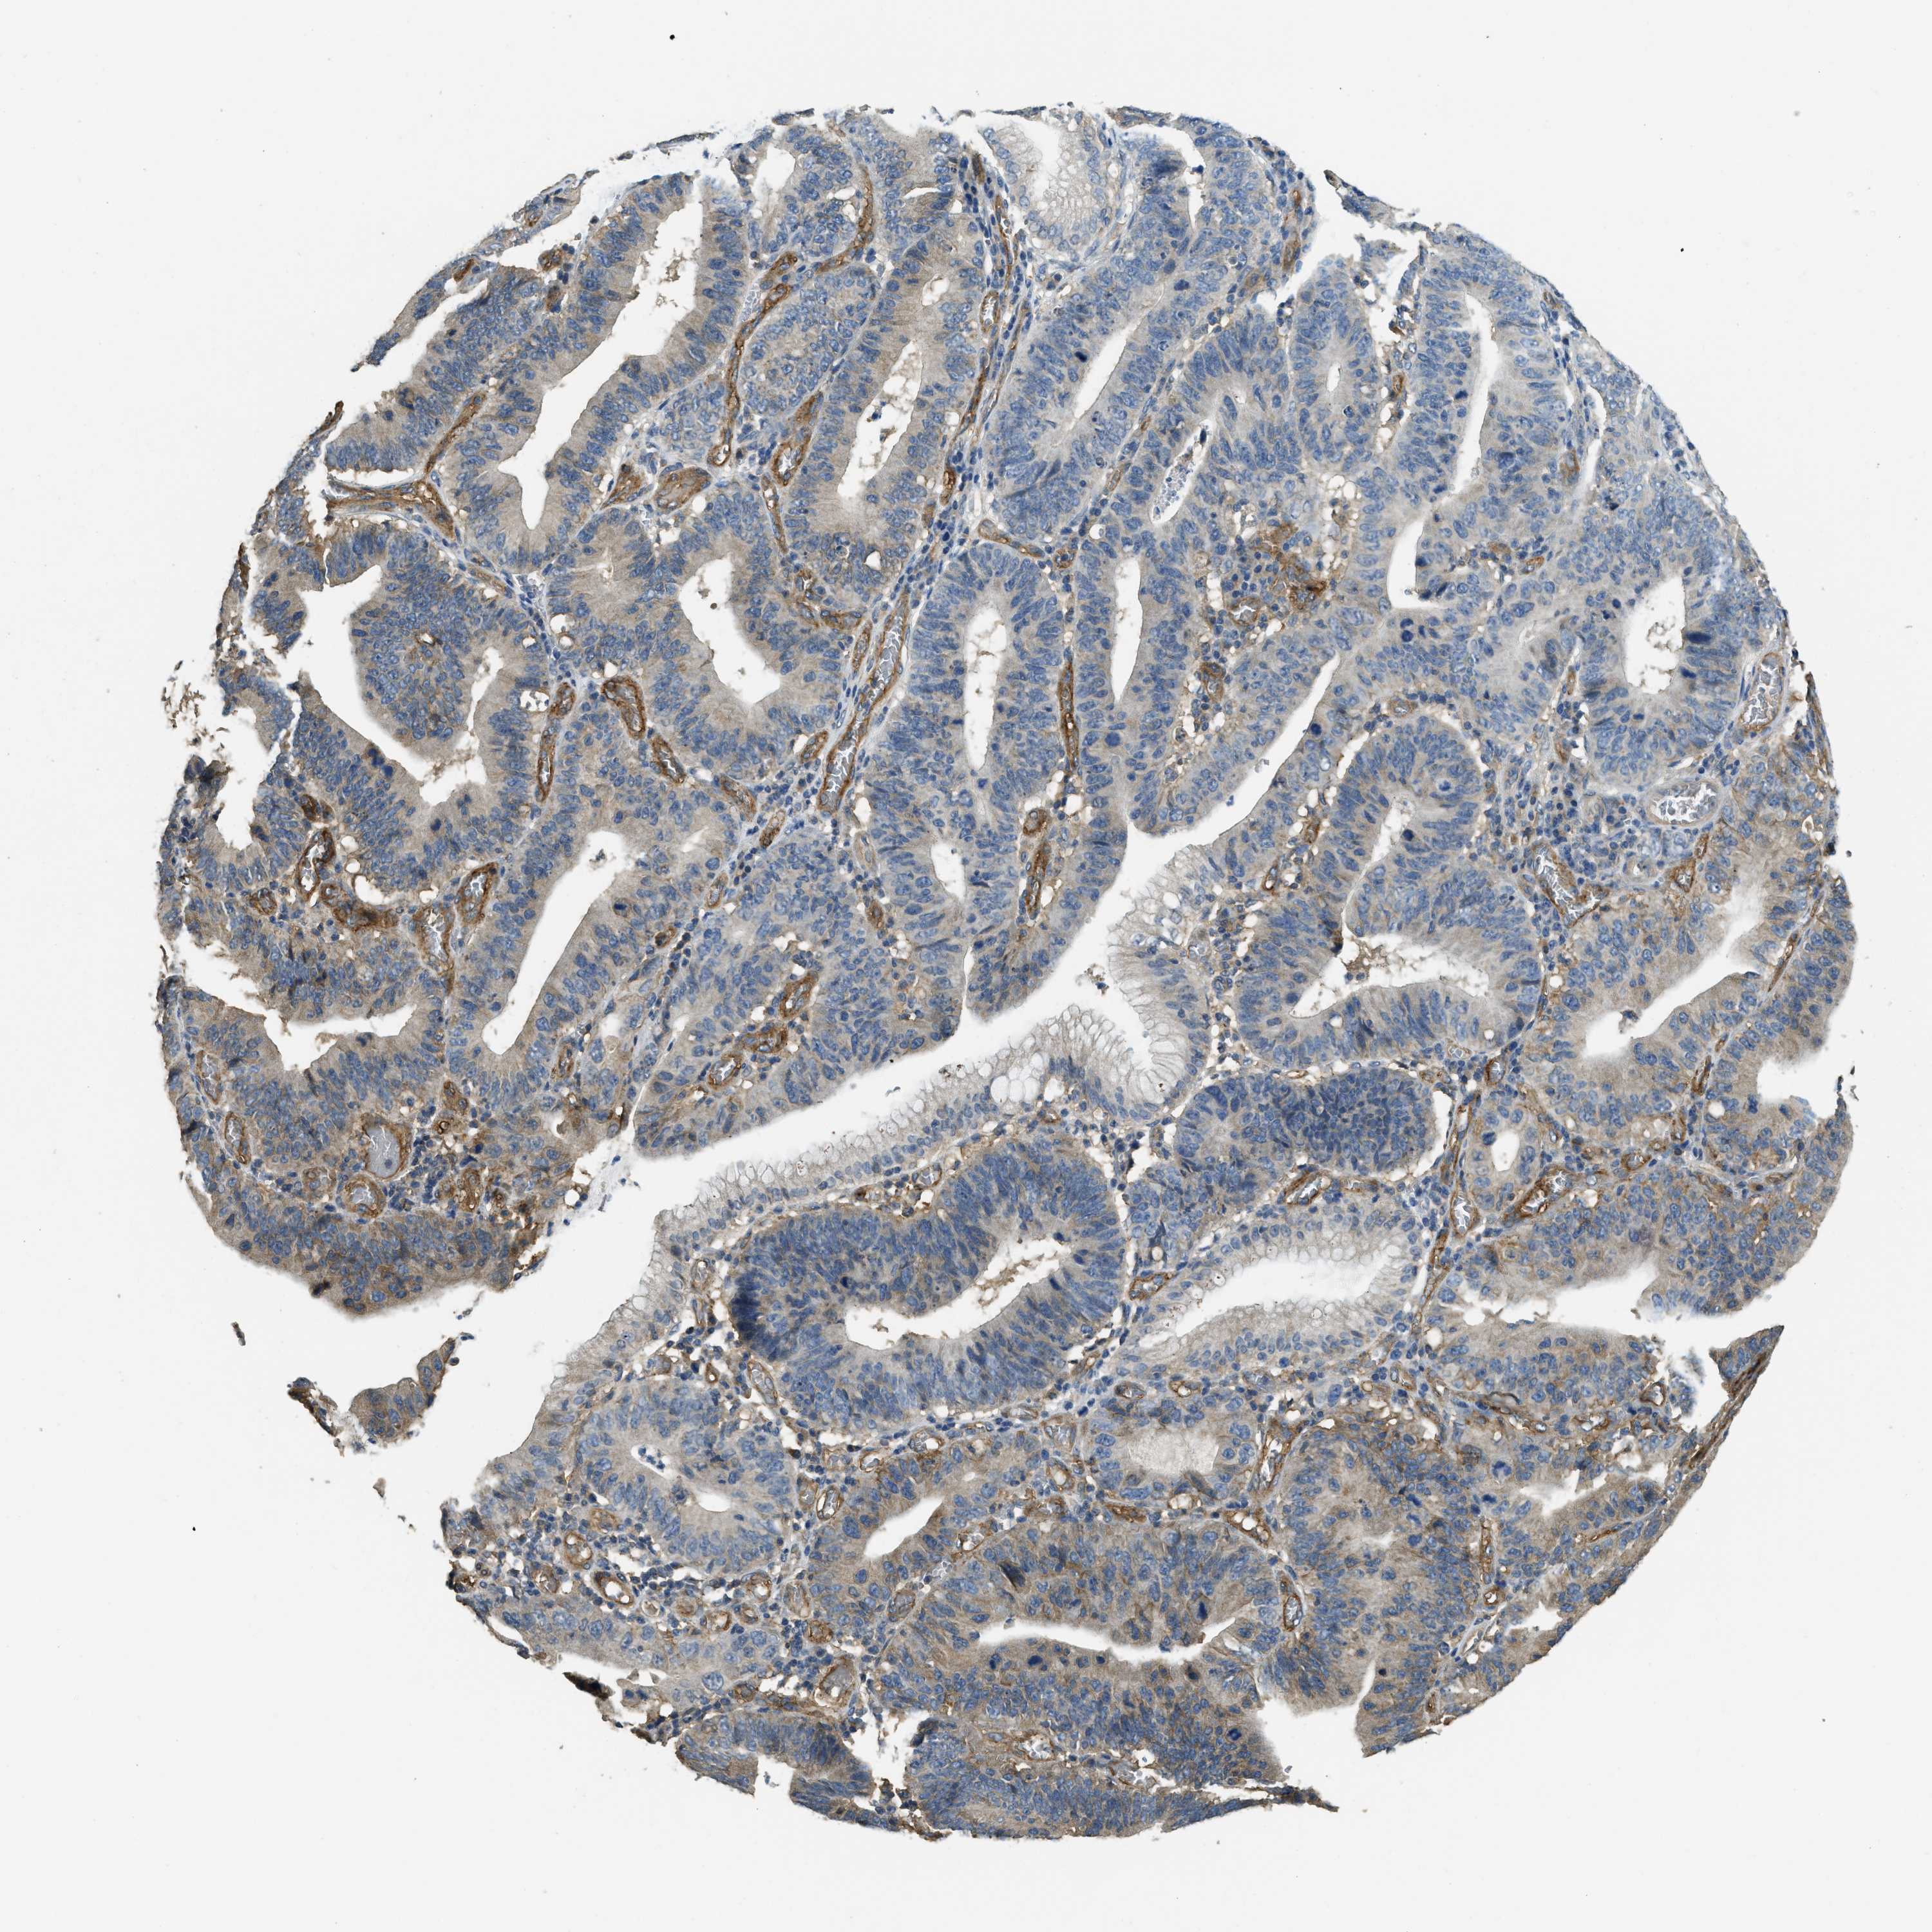

STOMACH CANCER - Protein expressioni

A mouse-over function shows sample information and annotation data. Click on an image to view it in a full screen mode. Samples can be filtered based on level of antibody staining by selecting one or several of the following categories: high, medium, low and not detected. The assay and annotation is described here.

Note that samples used for immunohistochemistry by the Human Protein Atlas do not correspond to samples in the TCGA dataset.

Antibody stainingi

Antibody staining in the annotated cell types in the current human tissue is reported as not detected, low, medium, or high, based on conventional immunohistochemistry profiling in selected tissues. This score is based on the combination of the staining intensity and fraction of stained cells.

Each image is clickable and will lead to virtual microscopy that enables deeper exploration of all samples and also displays staining intensity scores, fraction scores and subcellular localization as well as patient and tissue information for each sample.

Antibody HPA009285

Antibody HPA017139

Antibody CAB017826

Staining

High

Medium

Low

Not detected

Intensity

Strong

Moderate

Weak

Negative

Quantity

>75%

75%-25%

<25%

None

Location

Nuclear

Cytoplasmic/membranous

Cytoplasmic/membranous,nuclear

Adenocarcinoma, NOS

Adenocarcinoma, High grade